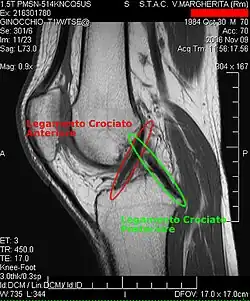

Knie (anatomie)

![]() | ||||

Linkerknie, gezien vanaf de achterzijde | ||||